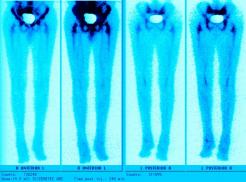

Nuclear Scan Images of Lower Torso & Lower Legs

These images were captured in order to determine why Liam’s bones broke so easily playing a video game and to also determine if there

was any Osteomyelitis. This is the diagnosis report from the scan. "There is mild increased activity noted in the lateral side of the left

ankle. However the patient does have a cast on the left leg. This uptake can be secondary to either inflammatory or infectious change within

either the skin or adjacent bone." Various contrast were used to enhance image details. The last images reminds one of the Shroud of Turin.

Hummm, makes one wonder... ;-)